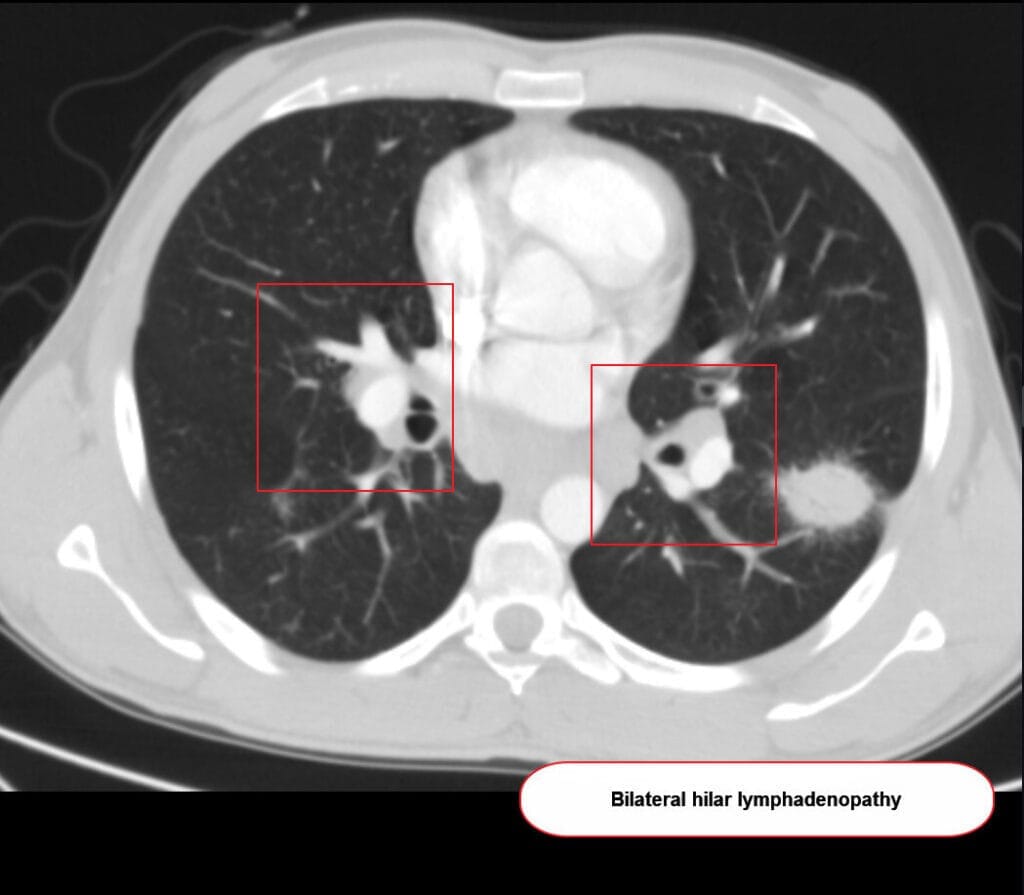

사르코이드증 (Sarcoidosis)

무증상 또는 기침·호흡곤란 + 양측 흉부 림프절 비대 + 비건락성 육아종

– 다양한 장기에 비건락성 육아종이 형성되는 원인 불명의 전신성 염증성 질환

– 폐와 림프절 침범이 가장 흔하지만 눈, 피부, 심장 등도 침범 가능

진단

– 흉부 X선에서 양측 폐문 림프절 비대; HRCT에서 육아종성 결절

– 조직검사에서 비건락성 육아종 확인; 결핵 등 다른 원인 배제

– 혈청 ACE 상승, 칼슘 증가, BAL CD4/CD8 비율 상승 등 보조지표

Hacking C, Sarcoidosis. Case study, Radiopaedia.org (Accessed on 01 May 2025) https://doi.org/10.53347/rID-38391